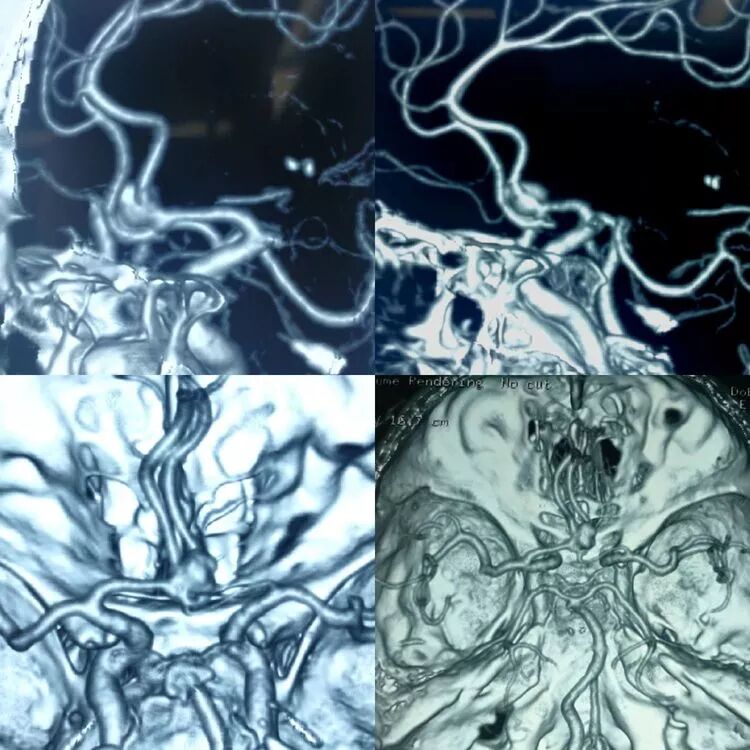

眶颧入路(Orbitozygomatic Craniotomy,OZ)扩展了额下入路的视野,减少了脑牵拉的必要,以获得前颅底宽阔暴露。该入路可提供从下至上的卓越视野和手术空间,同时也是一种高灵活度和自由度的手术入路。眶颧入路又分为“双骨瓣法”和“单骨瓣法”两种方式。

单骨瓣法额颞开颅加眶上骨切开术,即改良眶颧入路(Modified OZ),其创伤更小,具备其它眶颧开颅术式的主要优势。

前交通动脉复合体结构复杂,变异很大,动脉瘤位置和形态千奇百怪,对于动脉瘤指向后上方的前交通动脉瘤,可以使用翼点入路、眶上外侧入路和纵裂入路。通过美国Texas大学颅底神经外科中心冯栋侠教授的指导和介绍,得知美国神经外科医生会选择OZ入路完成此类手术。我们团队对于收治的一例瘤顶指向后上方的前交通动脉瘤选择了该入路完成动脉瘤夹闭手术,现在报告如下。